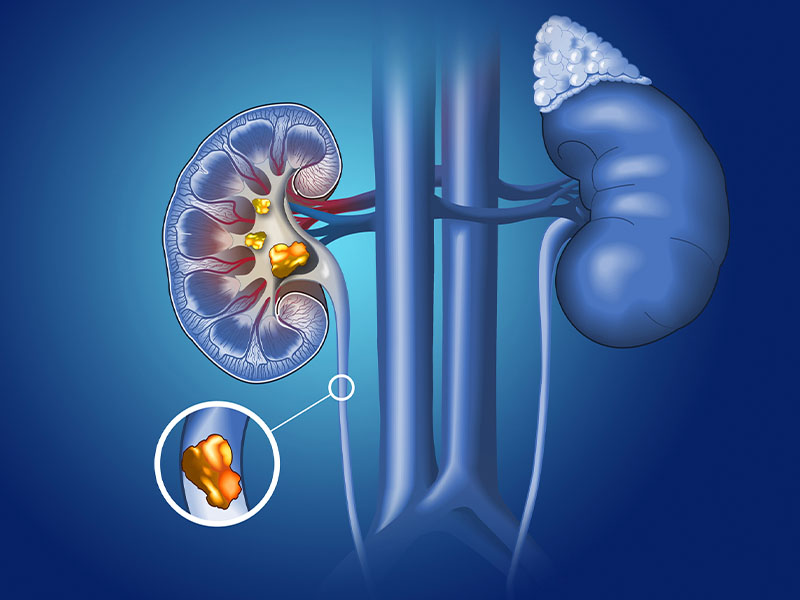

Hệ tiết niệu đảm nhận vai trò lọc các chất thải đẩy ra ngoài dưới dạng chất lỏng và lọc máu. Hệ tiết niệu bao gồm: thận, niệu quản, bàng quang, niệu đạo. Khi sỏi xuất hiện ở các vị trí trên thì sẽ được gọi là sỏi tiết niệu.

- Sỏi rơi từ thận xuống hai ống niệu quản và kẹt tại đây làm tắc đường tiểu. Khi nước tiểu không được đào thải ra ngoài sẽ gây bí tiểu và ứ nước ở thận. Lượng nước tiểu được thận bài tiết liên tục nhưng không thoát ra ngoài được lâu dần sẽ làm vỡ thận.

- Tình trạng ứ nước ở thận do sỏi gây ra kéo dài sẽ làm suy giảm chức năng thận. Thận có thể bị suy thận cấp tính hoặc mãn tính, khi rơi vào trường hợp này bạn cần thăm khám ngay. Vì khi thận suy yếu trầm trọng bắt buộc bạn phải chạy thận hoặc phẫu thuật thay thận.